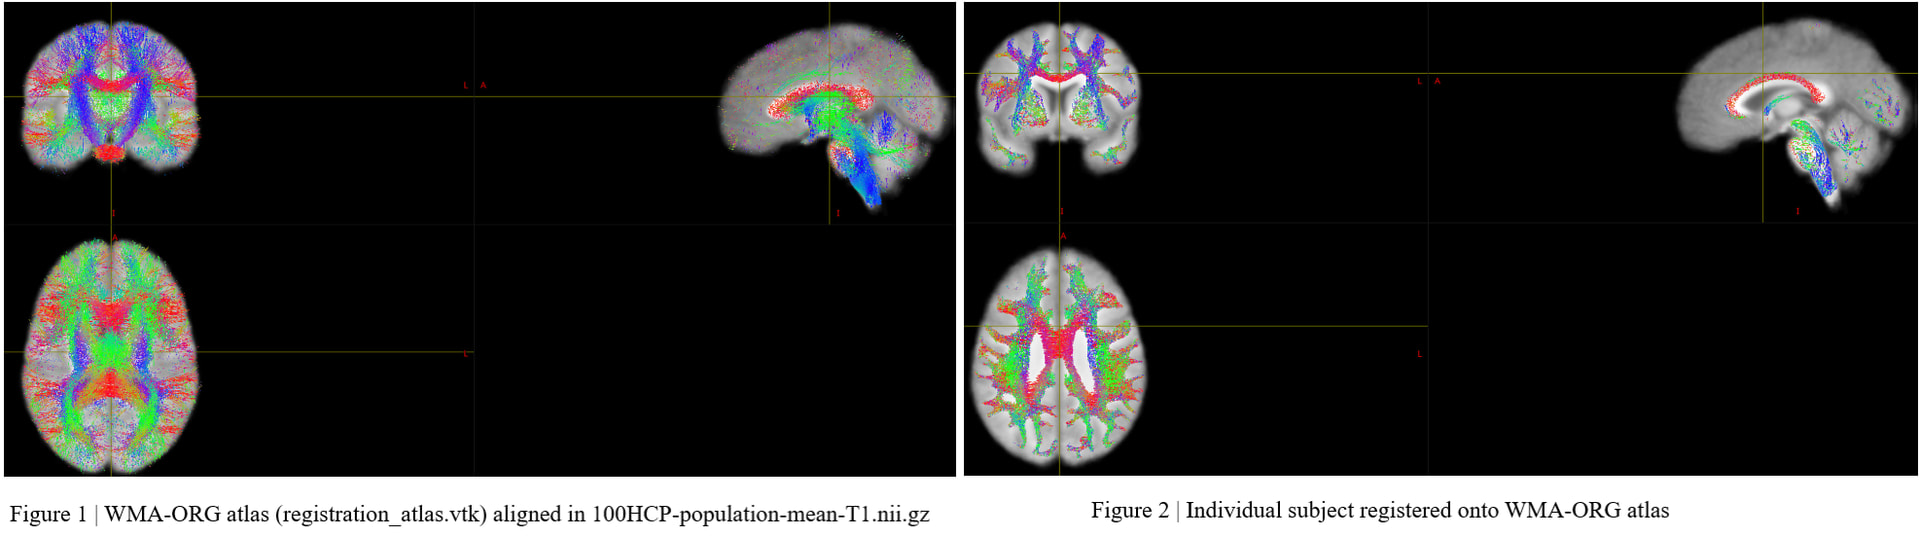

I have resolved the issue of transforming .tck files from individual space to template (ORG) space. My solution is as follows:

(1) First, we performed skull stripping on the T1w2dwispace.nii.gz image to obtain T1w2dwispace_brain.nii.gz.

(2) The skull-stripped image (T1w2dwispace_brain.nii.gz) was then registered to the T1_ORG_template.nii.gz using ANTs, yielding the transformation files (T1w2dwi_toTemplate_0GenericAffine.mat and T1w2dwi_toTemplate_1Warp.nii.gz).

(3) The resulting transformations were subsequently applied to the .tck files using tcktransform. However, due to differences between ANTs and MRtrix3 in how spatial transformations are represented and applied, additional conversion steps are required to ensure compatibility. A sample implementation is provided below for reference:

tcktransform "${TCK_IN}" mrtrix_tck_deformation.mif T_CC1_inTemplate.tck